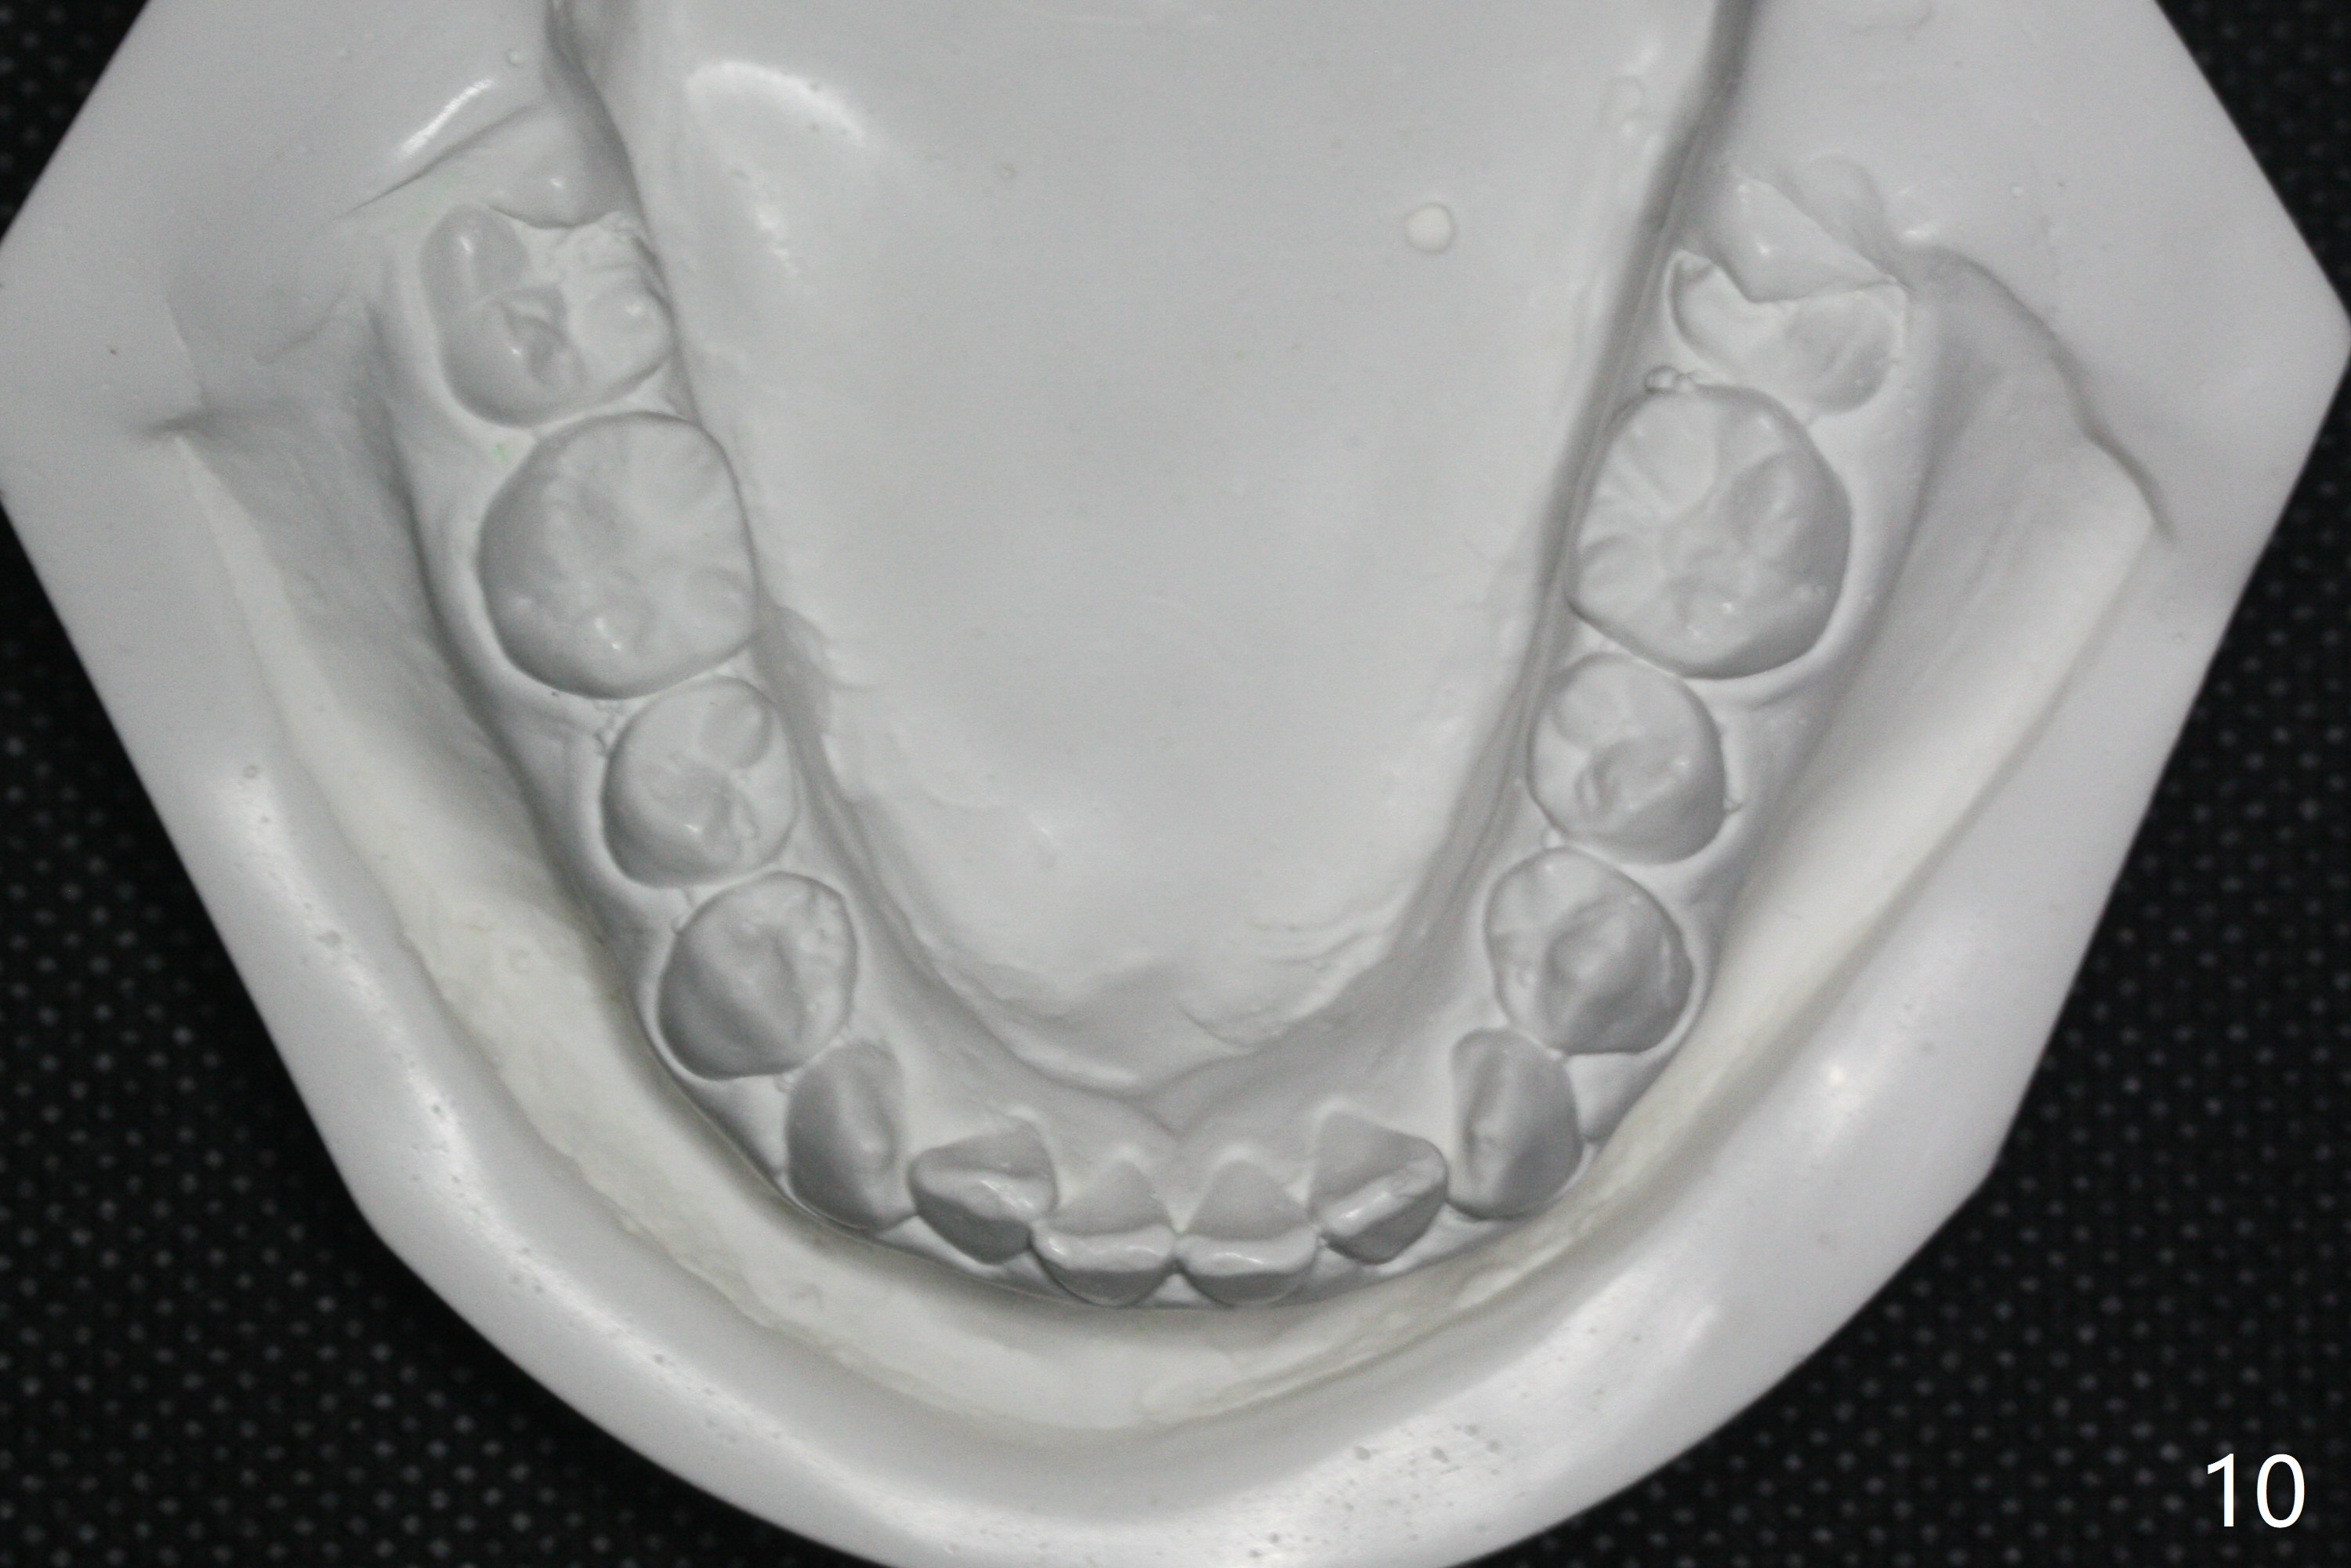

| Pre-op (11 y/o) | Post-op (12 y/o) | Follow Up (14 y/o) |

Relapse

A 11-year-old man starts orthodontic treatment and finishes in 9 months. Two years later crowding relapses because of loss of suck down retainers. It appears that lingual retainer is necessary.